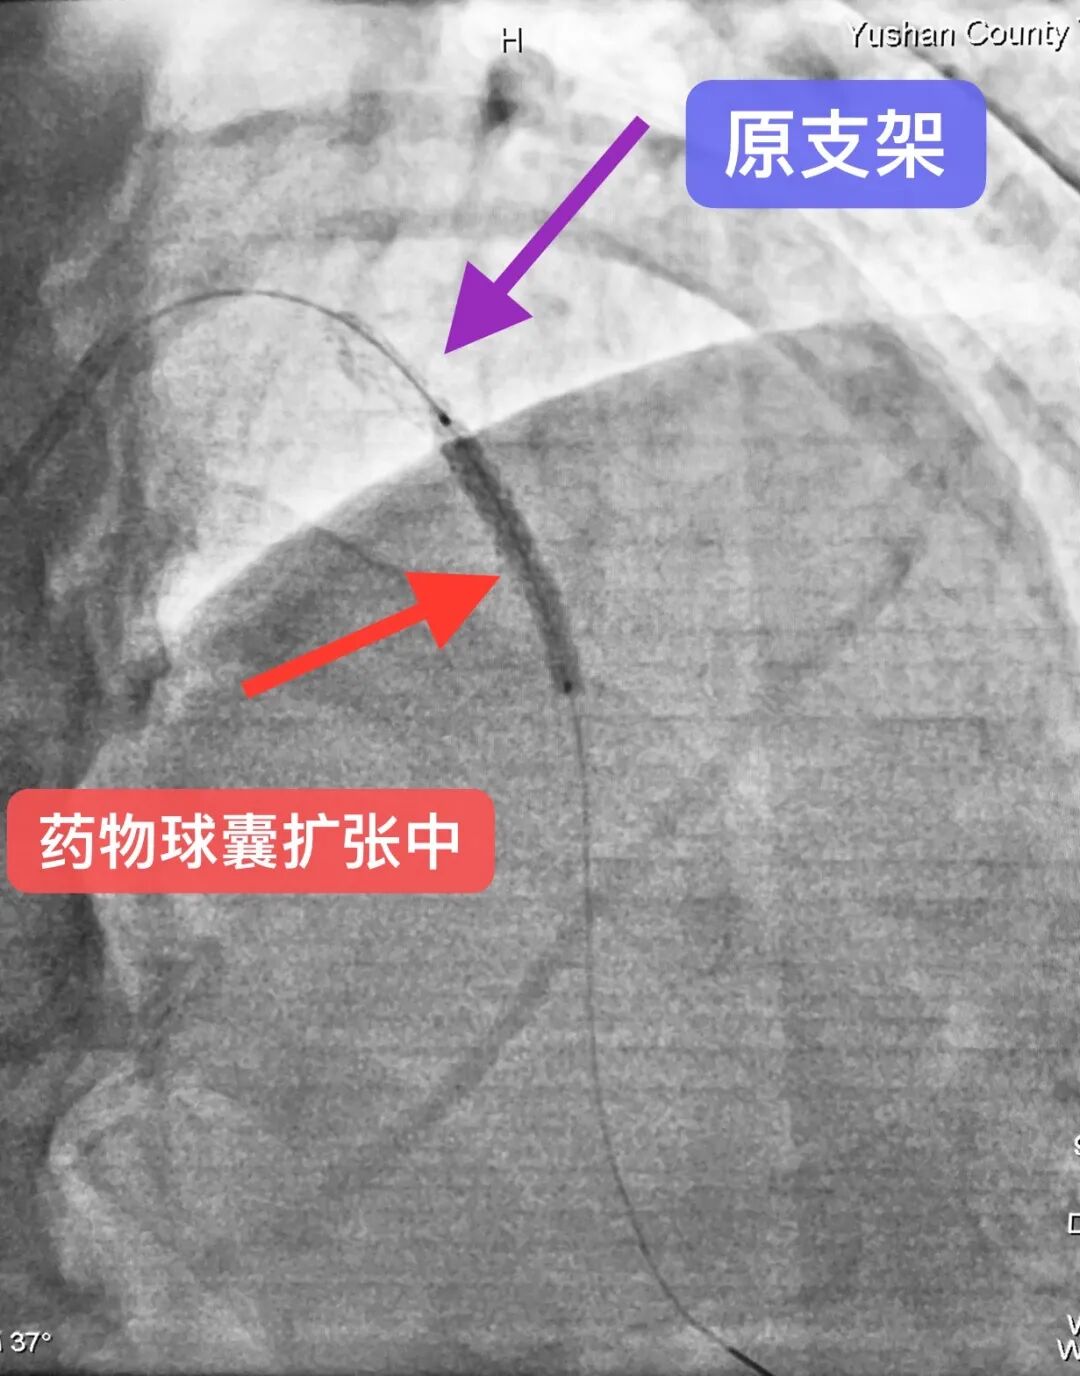

导读 心脏介入无植入,“药物球囊”显奇效!近日,县域首例支架内再狭窄药物球囊扩张术在玉山中医院顺利完成。 患者汪老伯,8年前因急性心梗在外院于前降支植入一枚支架,近一年反复出现胸闷、胸痛不适症状来县中医院就诊。经评估后考虑支架再狭窄可能,复查冠脉造影提示原支架内重度再狭窄。如在原支架内狭窄处叠加支架可能会明显增加再次狭窄风险,并且对血管弹性有明显影响,药物球囊扩张术是所有指南的优先推荐。经心脏介入科徐承权手术团队充分讨论并告知患者家属病情后,决定采用DCB(药物球囊)技术处理。术后患者症状即刻改善,立竿见影,3天后康复出院。

药物球囊的外表涂有一层可以抑制血管内皮增生的药物,医生通过患者手腕处的微小创口送入导管和药物球囊,用30至60秒的时间扩张球囊,把药物直接释放至冠状动脉的病变部位,在解除狭窄的基础上同时达到抑制血管内皮增生作用,保证血管通畅,降低再狭窄和血栓发生风险。 药物球囊与支架最大的不同在于没有任何金属植入物残留于患者体内,但是药物作用时间可以持续到手术以后的数月之久,这就解决了由于内皮增生导致的介入术后血管再狭窄的问题,为不适合支架植入的患者带来了福音。 药物球囊目前适用于: 1、支架内再狭窄,避免在支架内植入支架;2、小血管病变不宜植入支架者;3、有高出血风险患者,或需要缩短双联抗血小板治疗时间;4、分叉病变不宜植入支架患者;5、拒绝体内异物的患者。但也有临床研究认为,对于普通冠心病患者,也可考虑单纯药物球囊扩张,特别是糖尿病患者、年轻患者及高出血风险患者,因为糖尿病患者有较高的支架内再狭窄的比例;年轻患者由于年龄原因,对支架植入顾虑较多,甚至有抵触情绪;而高出血风险患者植入药物球囊后很短时间双抗后即可改为单抗治疗,避免了长期吃双抗带来的脑出血、胃肠道出血等致命风险。但药物球囊缺乏金属骨架因而不能预防急性弹性回缩的发生,亦不可用于处理血管夹层病变。 目前的临床随机对照试验已显示,在良好病变预处理基础上,结合功能学检测,DCB可有效抑制内膜增生,并有DAPT时间较短的优势,已成为许多临床情况下治疗冠脉病变的有效选择。DCB用于ISR治疗已是标准方案并得到指南推荐,不仅如此,DCB治疗冠脉新生小血管病变也被认为是DES的有效替代方案。此外,越来越多的证据表明,其它冠脉病变如分叉病变、大血管病变,甚至更复杂冠脉病变的介入治疗,都可能从单纯DCB治疗策略中获益。